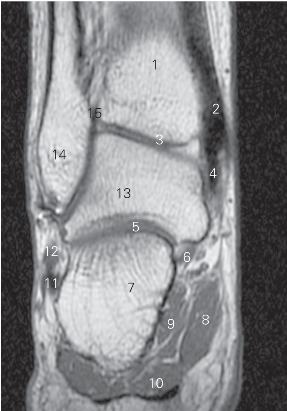

图5-45 经距下关节后份的横断层MR T1加权图像

1 胫骨 tibia 2 踝关节 ankle joint

3 胫跟韧带 calcaneotibial ligament 4 胫骨后肌 tibialis posterior

5 距下关节 subtalar joint 6

长屈肌 flexor hallucis longus

7

展肌 abductor hallucis 8 足底方肌 quadratus plantae

9 趾短屈肌 flexor digitorum brevis 10 跟骨 calcaneus

11 腓骨短肌 peroneus brevis 12 跗骨窦 sinus tarsi

13 距骨 talus

14 趾长伸肌 extensor digitorum longus

图5-46 经距下关节前份的横断层MR T1加权图像

1 胫骨 tibia 2 胫骨后肌 tibialis posterior

3 胫距后韧带 posterior tibiotalar ligament

4 趾长屈肌 flexor digitorum longus 5

6

展肌 abductor hallucis 7 足底方肌 quadratus plantae

8 趾短屈肌 flexor digitorum brevis 9 腓骨长肌 peroneus longus

10 腓骨短肌 peroneus brevis 11 距下关节 subtalar joint

12 胫腓后韧带 poterior tibiofibular ligament

13 趾长伸肌 extensor digitorum longus